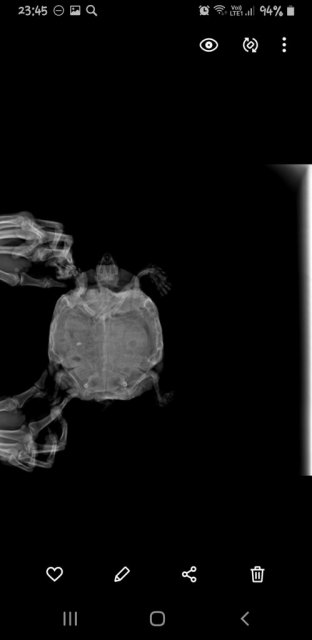

Александр Вдовин Ваше имя: Александр Локация: РФ, Самара Опубликовано: 24 августа 2024 Опубликовано: 24 августа 2024 Не знаю ее возраста, т.к. приползла ко мне на дачу 12 лет назад подростком Недели 3 назад обратил внимание на тяжелое дыхание(возвратно-поступательные движения передних лап с большой амплитудой). Примерно тогда же она стала мало есть и перестала какать. К тому же перестала использовать задние лапы Я живу в Самаре. Эти 3 недели я попадал к людям в ветклиниках, которые считают себя герпетологами. Намучали они моего питомца и отняли время, дарив пустую надежду Сегодня поехал в "Симсон", и черепахе сделали рентген в 3 проекция.Сказали, что всё ужасно. Подскажите сильно опасно ли в данной ситуации консервативное лечение? Возможно ли попасть на операцию к Дмитрию Борисовичу Васильеву без длительного ожидания, если уж без операции никак.Я оставил заявку на прием к нему на сайте " Белый клык" и не знаю увидит ли он её. Мне пока не ответили. К тому же сегодня суббота.Я теряю время. И в Москву я очень быстро добраться не смогу, т.к. мне на самолете нельзя летать.

Консультанты moth Ваше имя: Мария Локация: Москва Опубликовано: 24 августа 2024 Консультанты Опубликовано: 24 августа 2024 @Александр Вдовин здравствуйте! по рентгену тут действительно всё плохо в плане лёгких, их просто нет - они либо пережат содержимым жкт, либо какая-то другая проблема, тут уже должен непосредственно врач-герпетолог хороший смотреть. В Саратове есть хороший герпетолог-хирург, туда Вам проще доехать будет? https://cherepahi.ru/servisy/catalog/rossiya/spravochnik-saratovskaya-obl-saratov/ у них есть стационар, где можно черепаху на лечение оставить

Александр Вдовин Ваше имя: Александр Локация: РФ, Самара Опубликовано: 29 августа 2024 Автор Опубликовано: 29 августа 2024 Какие еще косвенные признаки бывают? Газов у нас на снимке не наблюдается,но легкие как будто чем-то прижаты. Хотя нам Валерия Николаевна пневмонию продиагностировала Поэтому точно узнать прижаты они или поражены точно определить сложно. Пневмония только снизу - тоже странно А чем они бывают прижаты ещё, кроме газов кишечника? Не могу найти информацию нигде Вот снимки. Очень похоже, что они с разными настройками

Консультанты moth Ваше имя: Мария Локация: Москва Опубликовано: 29 августа 2024 Консультанты Опубликовано: 29 августа 2024 @Александр Вдовин тут само качество снимков плохое и мелкое из-за разрешения телефона. Лёгкие могут быть пережаты не только газами, но и скоплением кала в жкт, увеличенным мочевым пузырём. Тут придётся кт ждать.